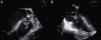

The unusual presence of vegetation at the VSD and the characteristic prolapse of the right aortic cusp with the attached vegetation (Figure 2) were confirmed by transesophageal echocardiography.

Transesophageal echocardiography (TEE). (A) TEE at 131° disclosing a vegetation attached to the VSD protruding into the right ventricle (orange arrow) with prolapse of the right aortic cusp and the vegetation attached to the VSD. (B) TEE at 0° shows the aneurysm of the septal leaflet of the tricuspid valve (white arrow) and the vegetation on the atrial side (yellow arrow).